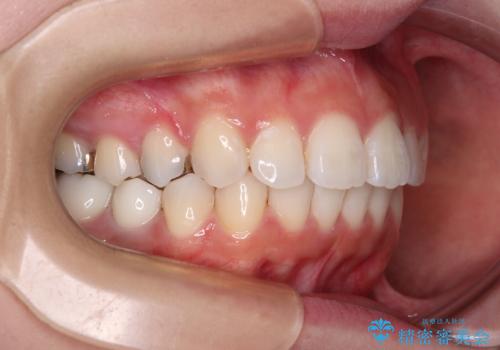

欠損した歯と前に飛び出した前歯 インプラント治療を併用したワイヤー矯正治療

- 上の前歯が下唇に当たる感覚と奥歯の欠損を気にして来院された患者様です。

上顎前歯の突出感は、上顎全体が前方に位置していることが原因であったため、補助装置により上顎全体を後方に移動させることとしました。

後方移動と同時上下歯列をワイヤー装置にて整え、奥歯の欠損部には矯正治療の途中でインプランを埋入していくこととしました。

上顎歯列全体を後方移動させたことで唇に当たる感覚は改善され、更には上下の正中位置も合わせることができました。